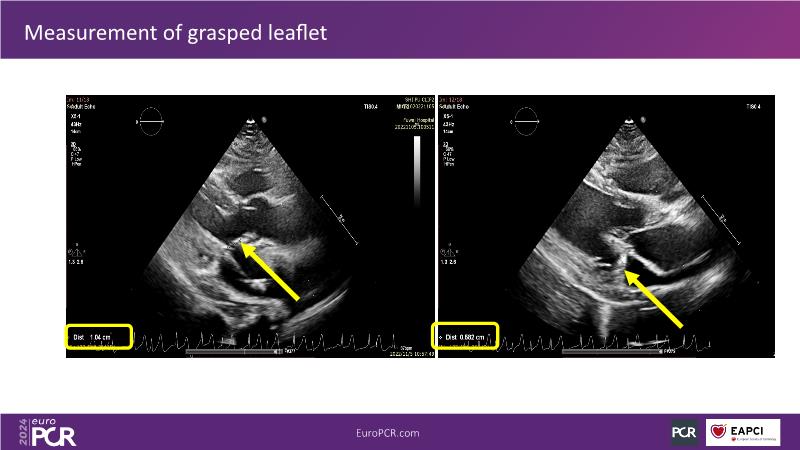

Watch this session to gain insights into the clinical evidence of mitral TEER therapy for the Asian population, learn techniques for implanting a MitraClip in patients with challenging anatomy, and understand how to use the four clip sizes for optimal outcomes. The session also covers educational aspects of clipping in dextrocardia, the benefits of reserve bending of the transseptal needle for tenting and puncture, new steering maneuvers for dextrocardia patients, and the importance of understanding anatomy and collaborating closely with the echo team for success.